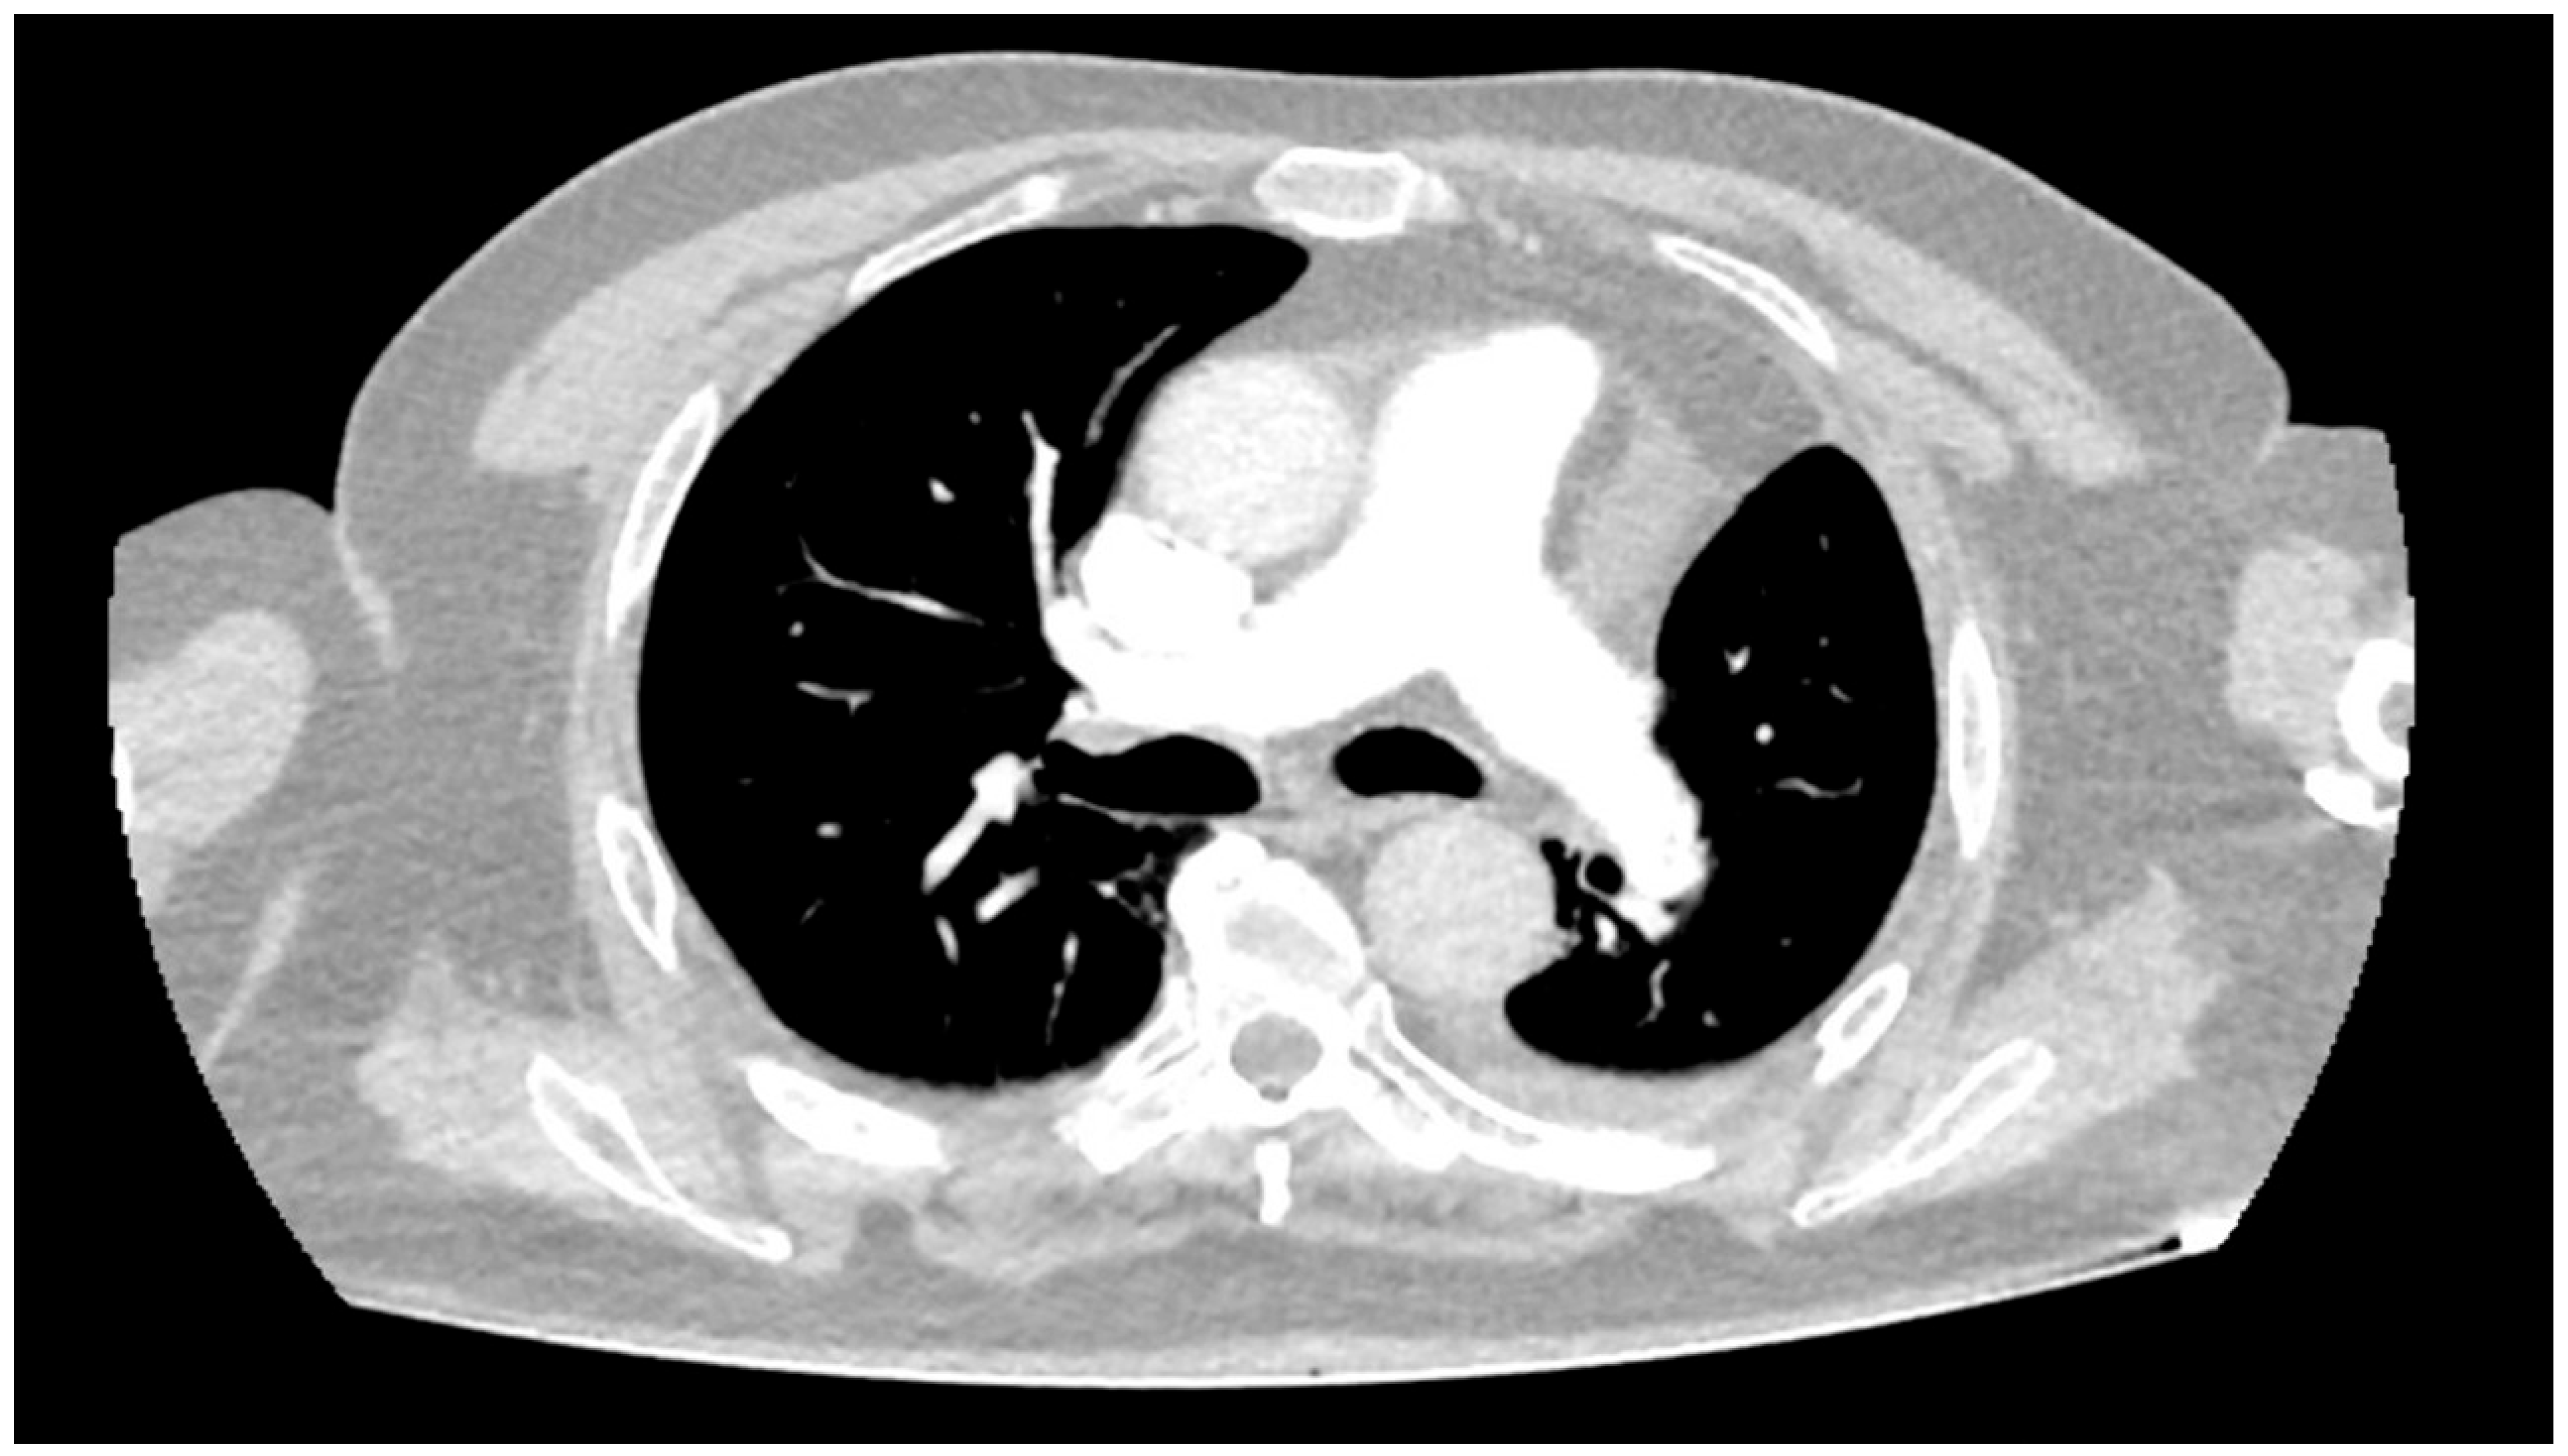

2. Detailed Case Description